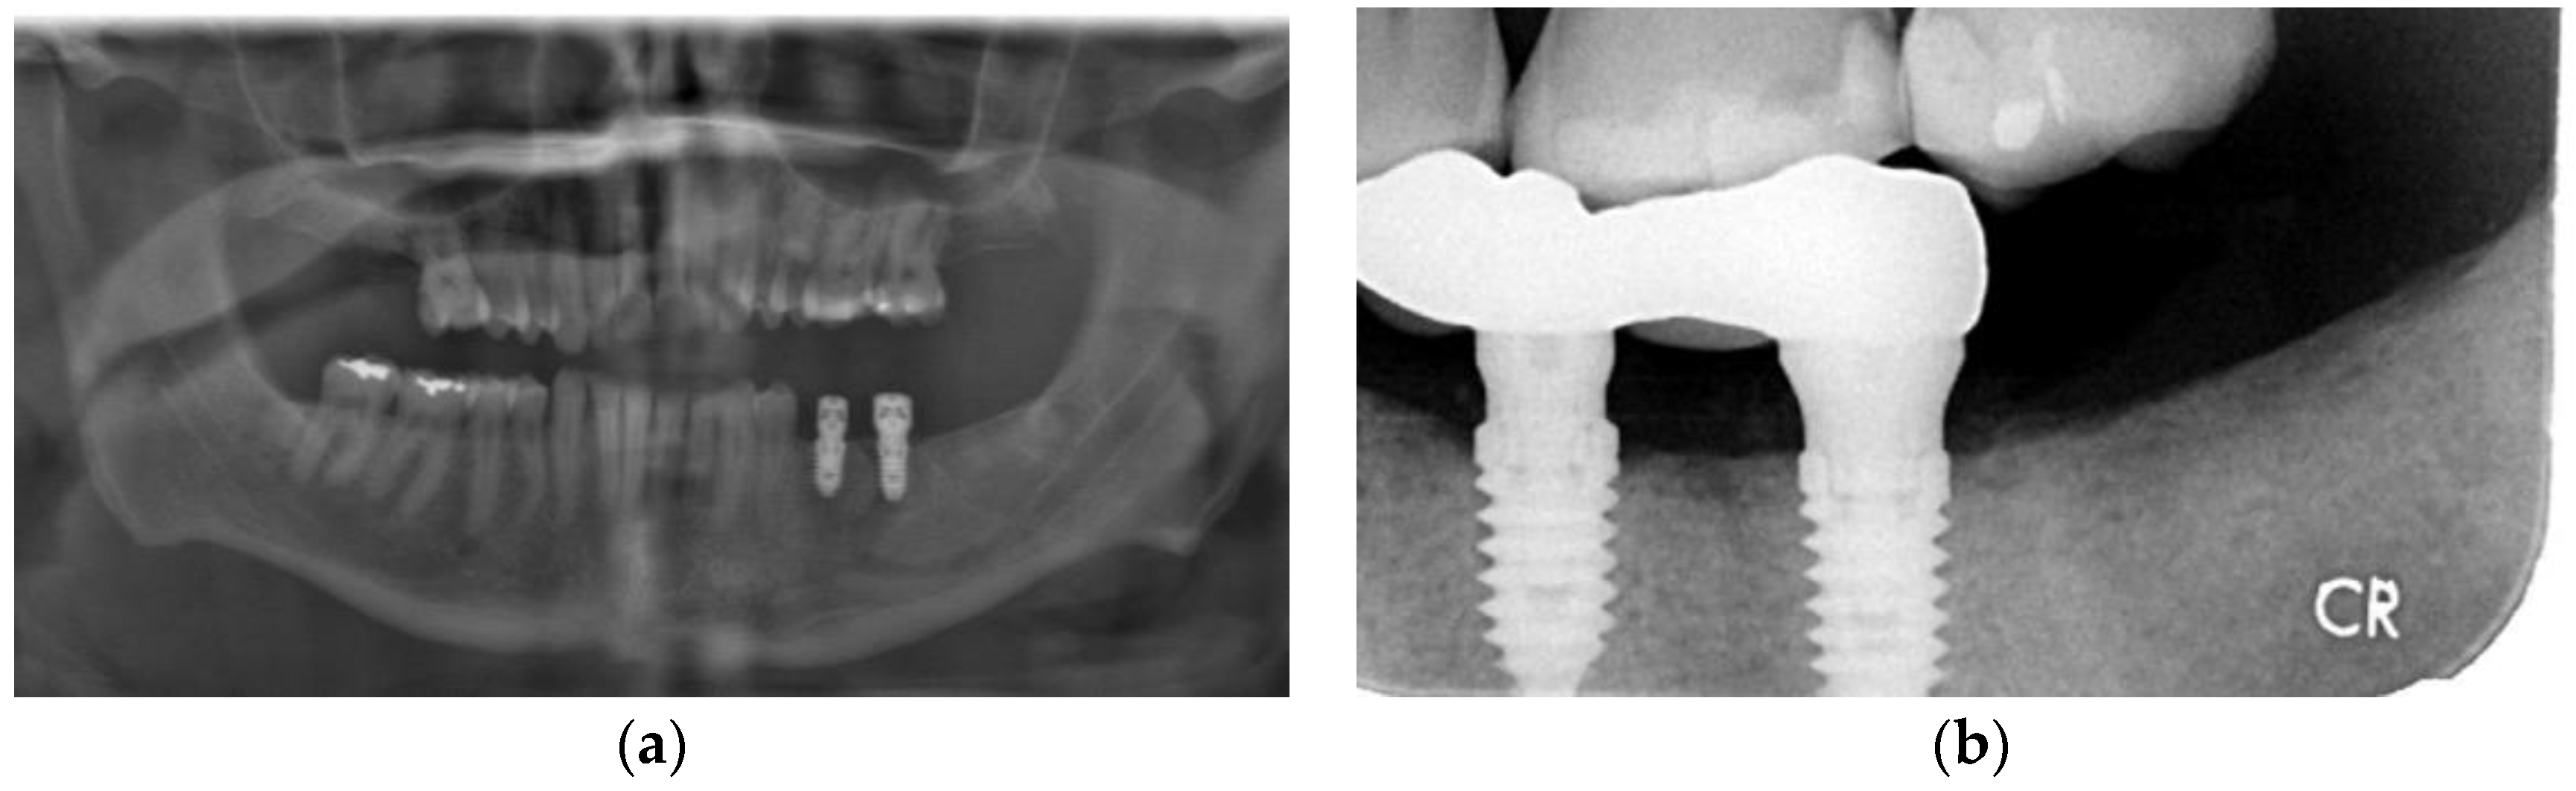

3.4. Case 4

3.5. Case 5